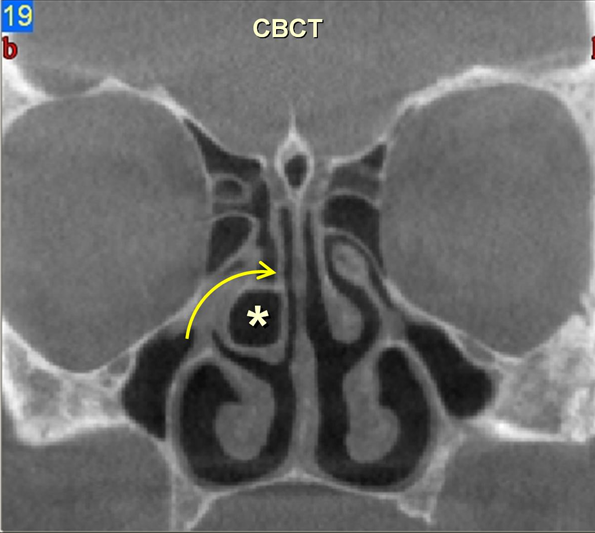

3. image: Paranasal sinus examination, coronal reconstructions (right panel: cone-beam CT; left panel: MDCT). Concha bullosa(asterisk) with ethmoidal infundibulum narrowing (arrow). Cone-beam CT and MDCT information correlates almost 100 %.